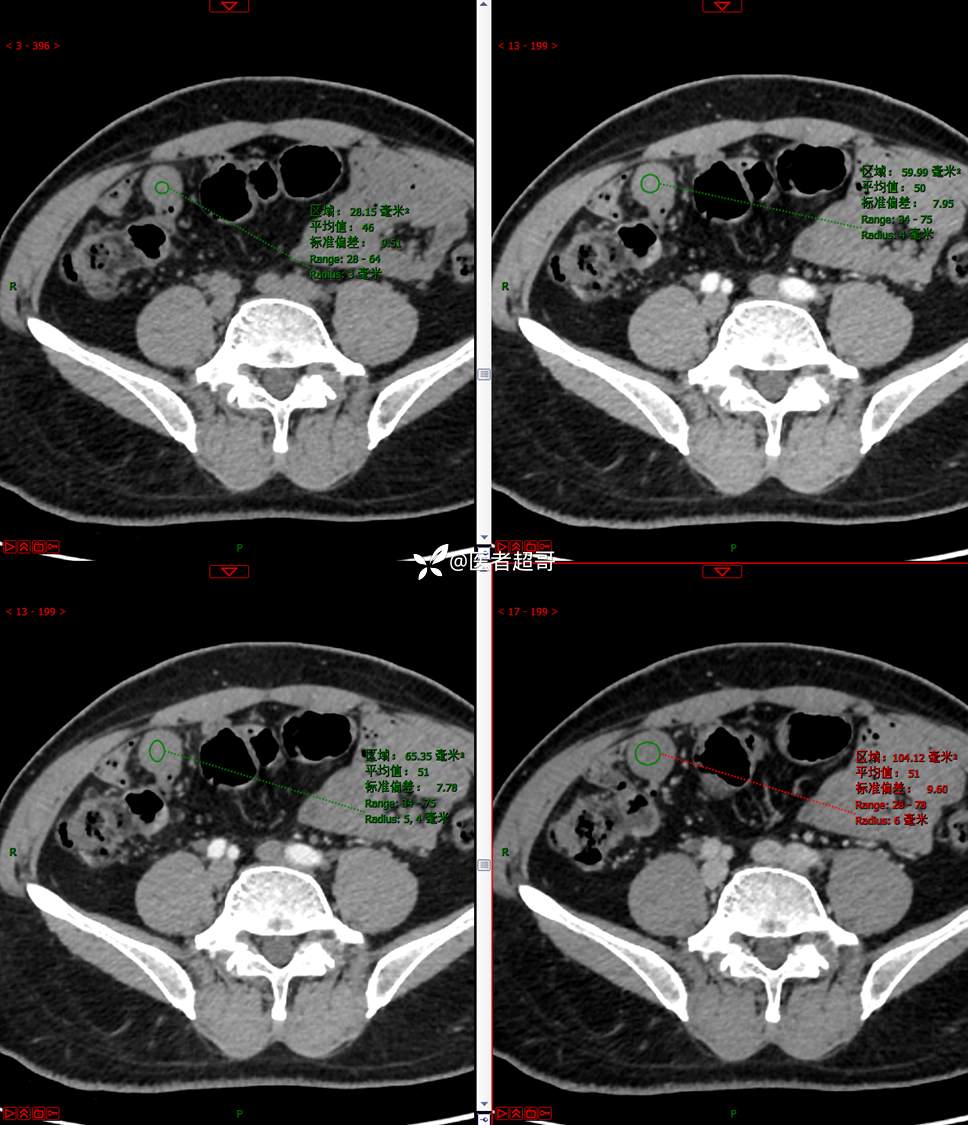

【影诊笔记747】结节不大,挺有意思的,做手术了,请赏析!

男,48岁 0200608 01

主诉:腹痛1月余。

现病史:患者1月余前无明显原因及诱因出现腹痛,脐周为著,为持续性隐痛,无发热,无恶心、呕吐,无腹泻,伴反酸,无胸闷、憋气,无呕血、黑便,至我院门诊就诊,查肝胆胰脾肾彩超诊断:肝胆胰脾双肾未见异常,下腹部实性团块,建议进一步检查,血淀粉酶46U/L,血常规未见明显异常,自服“肠炎宁”药物治疗,效果欠佳,现患者为行进一步治疗,门诊以“腹痛待查 腹腔肿物”收入院。患者自发病以来,神志清,精神可,饮食、睡眠可,大小便正常,体重较前无明显减轻。